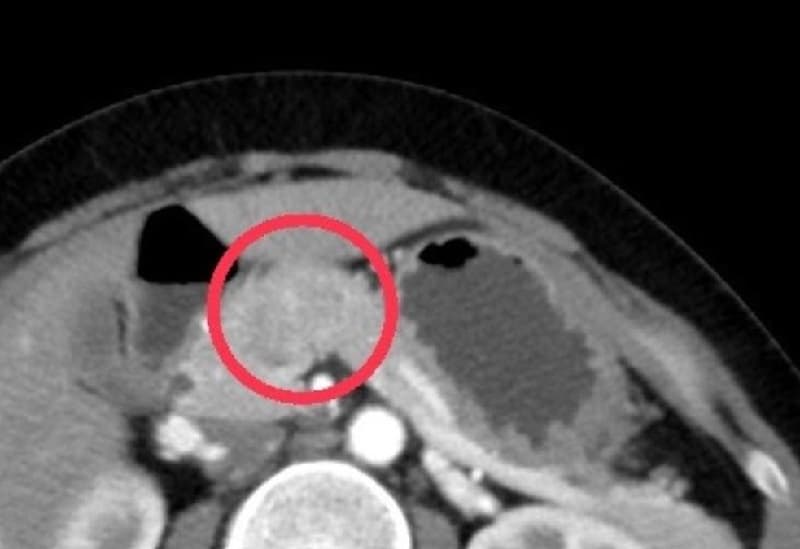

- Chụp cắt lớp vi tính (CT)

CT sử dụng tia X đa lát cắt để tái tạo hình ảnh rõ nét của tụy và các cơ quan lân cận. Phương pháp này không chỉ giúp phát hiện khối u mà còn đánh giá mức độ lan rộng, từ đó xác định khả năng phẫu thuật.